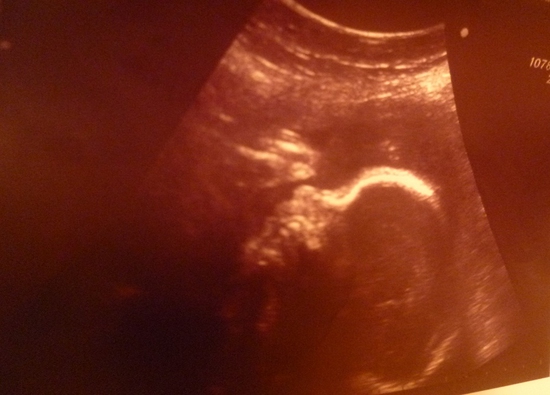

в общем девочки выбежала я опять вся в слезах,а дома меня такая истерика накрыла,что я вобще от слез задыхалась.мама,когда узнала,сразу же сказала ехать в липецк к другому специалисту,в общем так мы втроем,я ,муж и мама поехали туда на очередное узи.всю дорогу я молилась,лишь бы не услышать вердикт врача,что надо прервать Б,этого я бы не пережила(вот мы приехали в центр узи,врач долго и тщательно мне его делала,а дочь в это время сосала пальчик)в итоге врач сказала,что у меня действительно маловодие и малышка мало весит и отстает на неделю в развитии,но все остальное в норме и нет никаких патологий.но лечить маловодие надо и дочку,чтоб она набрала вес.после узи мы сразу пошли к г,которая к счастью оказалась врачом из роддома,где я собираюсь рожать,она выслушала всю мою историю,посмотрела узи,смерила с чем то,и в итоге сказала,что малышка отстает только в весе,и назначила мне лечение.уехала я оттуда с таким облегчением,словами не передать,и дала себе слово,что больше ни зачто не пойду к таким врачам как баранова,из за ее диагнозов реально от нервов сойти с ума можно..вот такие дела девули,несколько дней я в себя прийти не могла,голова болела ужасно..сейчас мне делают капёльницы,и я верю,что моя принцесска скоро наберет вес)а вот и наша любимочка))